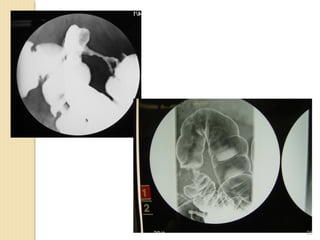

Double contrast barium enema: This is an x-ray test of the colon and rectum.

Angiography

Angiography is an x-ray procedure for looking at blood vessels. Contrast medium, or dye,

is injected into an artery before x-ray images are taken. The dye outlines the blood vessels

on x-ray pictures.

If your cancer has spread to the liver, angiography can be useful in showing the arteries

that supply blood to those tumors. This can help surgeons decide if the liver tumors can be

removed and if so, it can help in planning the operation. Angiography can also be helpful

in planning other treatments for cancer spread to the liver, like embolization

Angiography can be uncomfortable because the doctor who does the procedure has to put

a small catheter (a flexible hollow tube) into the artery leading to the liver to inject the

dye. Usually the catheter is put into an artery in your inner thigh and threaded up into the

liver artery. You have to hold very still while the catheter is in place. A local anesthetic is

often used to numb the area before inserting the catheter. Then the dye is injected quickly

to outline all the vessels while the x-rays are being taken.

Angiography may also be done with a CT scanner (CT angiography) or an MRI scanner

(MR angiography). These techniques give information about the blood vessels in the liver

without the need for a catheter in the leg artery, although you may still need an IV line so

that a contrast dye can be injected into the bloodstream during the imaging.